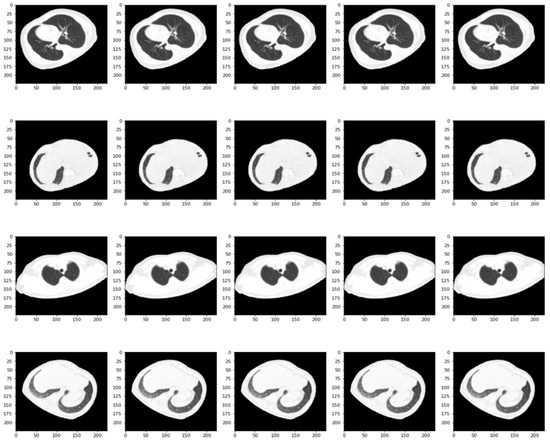

2.1. Data Collection and Pre-Processing

- CT-COV19 [22]—via IRB approval, CT-COV19 is a dataset of approximately 13,000 non-contrast lung CT scans in which chest cavity volume reconstructions are set at a slice thickness between 0.3 and 1 mm;

- COVID-19-CT [24]—all CT scans are classified into novel coronavirus pneumonia (NCP) due to the SARS-CoV-2 virus, common pneumonia, and normal controls being available globally to help clinicians and researchers fight the pandemic, where COVID-19 is making its presence felt;

- COVID-CT [25]—contains 349 CT samples belonging to 216 patients diagnosed positive for the COVID-19 virus and 397 CT images, with a negative diagnosis for COVID-19 having origins in bioRxiv and medRxiv servers;

- SARS-CoV-2 Ct-Scan-Dataset [26]—contains 1252 positive CT scans for SARS-CoV-2 (COVID-19) infection and 1230 CT scans for patients not infected with SARS-CoV-2, totaling 2482 samples collected from real patients in hospitals in Sao Paulo, Brazil.